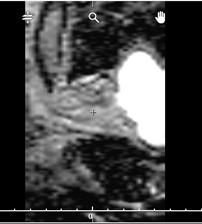

Comment le constater : Au moment de l'affichage du volume DICOM en page "Contour", le volume est affiché inversé sur l'axe apex-base. La position de la vessie est un point de repère efficace : "à gauche", le volume est affiché correctement, "à droite", le volume est affiché inversé.

| Image affiché correctement : la vessie est à gauche | Image affichée inversée : la vessie est à droite |